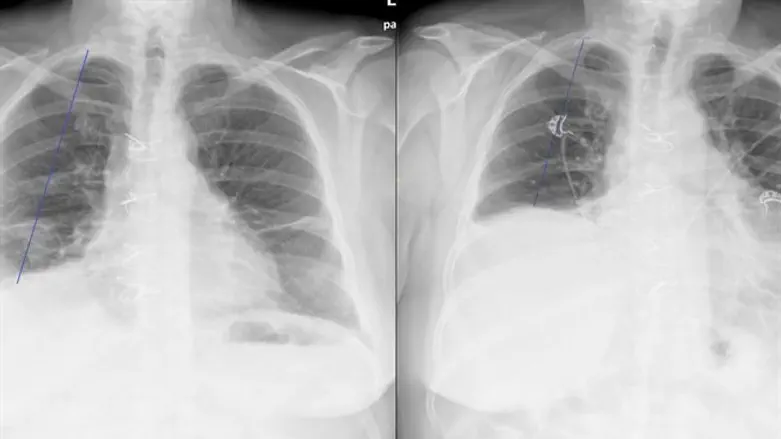

שטיינברג הגיעה לבירורים במחלקת כירורגיה חזה שבאיכילוב ולאחר בדיקות שנערכו לה, אבחן ד"ר עזאם שרבל שמדובר בשיתוק נדיר מאוד של עצם הסרעפת אשר גורם לקושי בנשימה.

ד"ר פאר מיכאל מנהל מחלקת כירורגיה חזה שבאיכילוב ומחלוצי תחום ניתוחים פולשניים בגישה רובוטית בישראל מדגיש כי הניתוחים בגישה זו שינו את כללי המשחק. "טכניקה ניתוחית זו מהווה פריצת דרך למטופלים הסובלים משיתוק של הסרעפת. אם בעבר מטופל היה זקוק לשיקום ארוך אחרי פתיחת חזה בעזרת חתך אמצעי או צדדי הרי שהיום מדובר בניתוח זעיר פולשני עם קיצור שהייה בבית החולים עד 2-3 ימים בלבד".